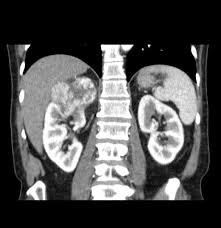

Kidney Tumor On Ct Scan. He also sent me for ct scan to get a clearer view turns out they spotted something on a kidney. Some patients however may need a biopsy.

He also sent me for ct scan to get a clearer view turns out they spotted something on a kidney. Typically these are detected incidentally in other words the patient has a scan for an unrelated problem and a tumor in the kidney is found. It this were indeed a kidney cancer it would be nearly impossible for it to have spread at that size.

Not all growths on. Kidney tumor contained within the kidney small kidney tumor 4cm increasingly we are detecting these small kidney tumors due to the increased use of ultrasound ct scan and mri. It this were indeed a kidney cancer it would be nearly impossible for it to have spread at that size. On imaging they have a variety of radiographic appearances from solid and.